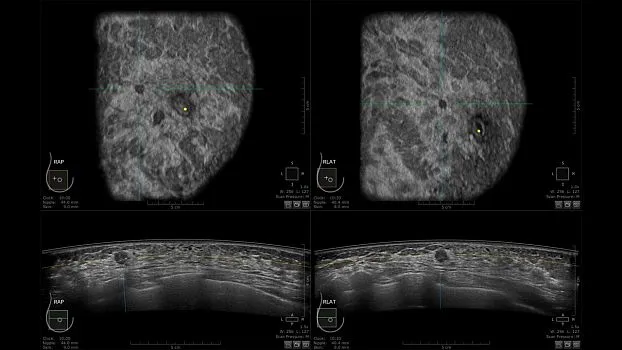

Клинические изображения

• Получение объемных 3D изображений с возможностью покадрового просмотра

• Отображение объемных 3D ультразвуковых изображений, которые состоят из традиционных поперечных и воссозданных коронарных и сагиттальных проекций

• Многооконный просмотр: 4 - 12 изображений.

• Одновременный просмотр двух изображений для сопоставления в коронарной плоскости

• Максимально операторонезависимая процедура, автоматическое 3D сканирование, толщина коронарного среза 2 мм.